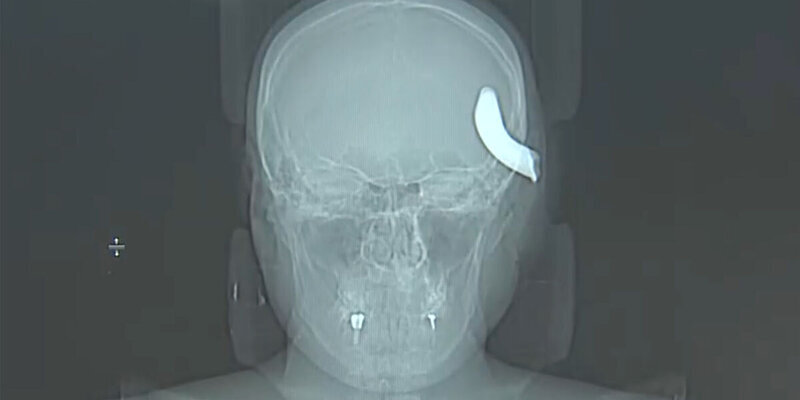

В Петербурге нейрохирурги извлекли из черепа молодого мужчины металлический крюк от буксировочного троса

Несчастный случай произошел в Приморском районе в апреле, когда мужчина решил помочь другу с буксировкой автомобиля. Когда машину тянули, зацепив тросом, крюк на нем размером 6х4 см не выдержал, оторвался и с силой отлетел прямо в голову Никиты. Так, с металлическим крюком в голове, пострадавшего и доставили во второе нейрохирургическое отделение больницы.

Хирурги в экстренном порядке отправили пострадавшего на операционный стол, провели ему декомпрессивную трепанацию черепа и удалили металлический фрагмент. Операция длилась три часа.